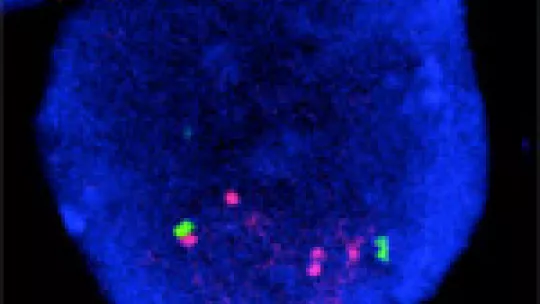

Aproximadament el 30% dels pacients amb càncer de mama presenten tumors que creixen i s’escampen per l’organisme d’una manera extremadament ràpida. Un denominador comú a tots ells és la presència d’una gran quantitat de proteïnes Her2 en les seves membranes cel·lulars, el que ha fet que aquests tumors agressius s’anomenin HER2 +. Científics del Laboratori de Metàstasi (MetLab) de l'IRB Barcelona liderats per l'investigador ICREA Roger Gomis han descrit els mecanismes moleculars que fan que els tumors HER2 + fugin de les senyals que protegeixen les cèl·lules d’un excés de creixement. El treball es publica aquesta setmana a la revista especialitzada Cancer Research.

Algunes molècules de fora de les cèl·lules s’uneixen a les proteïnes de membrana de la família Her fent que les cèl·lules es divideixin. No obstant, la presència de múltiples còpies del gen de Her2, com és el cas dels pacients HER2 +, fa que es divideixin sense control i sense respectar els senyals del seu entorn. La situació d’aquest subtipus de pacients HER2 + va canviar dràsticament fa més de 10 anys, quan va sortir al mercat el fàrmac Herceptin, que s’uneix a HER2 per impedir la seva acció proliferativa, el que es tradueix en una millor prognosi i major supervivència.

Mitjançant experiments realitzats amb cèl·lules metastàsiques procedents de pacients i models animals els investigadors han descobert que Her2 no només accelera la divisió cel·lular sinó que també fuig d’aquests sistemes de frenada. Her2 estimula la producció de la proteïna Lip, que desactiva els mecanismes que impedeixen la divisió cel·lular regulada per TGF-β i la senescència regulada per OIS, el que provoca una acceleració de la divisió. "Lip és el dolent de la pel·lícula. Afecta la funció de TGF-β i OIS, que són mecanismes de supressió de tumors ", explica Gomis.